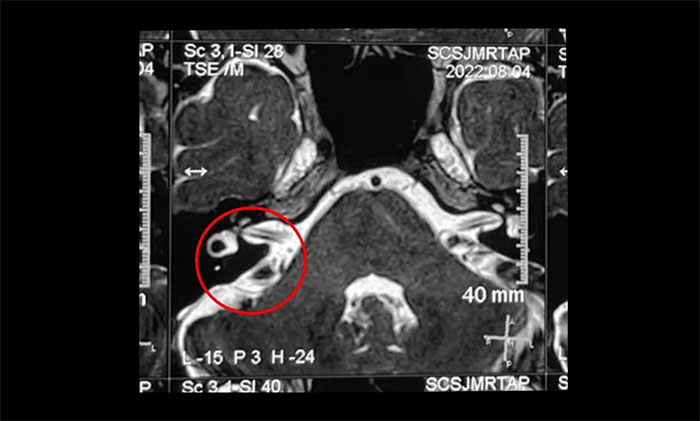

▲ 右侧三叉神经与周围小血管关系密切

结合影像资料,杨忠旭教授指出患者右侧三叉神经与周围小血管关系密切,手术指征明显,未见明显手术禁忌症。